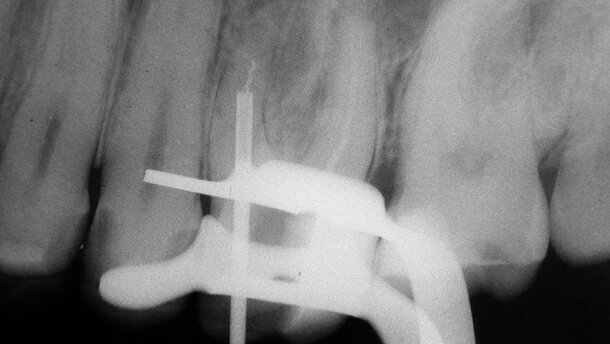

Fig. 5a_Radiographie préopératoire de la dent 26 montrant un instrument fracturé positionné dans la partie moyenne d’un canal radiculaire MV courbe.

Fig. 5b_Trépan de calibre 90 entourant le fragment.

Figs. 5c–d_Fragment bloqué à l’intérieur du trépan et retiré du canal.

Fig. 5e_Radiographie finale.